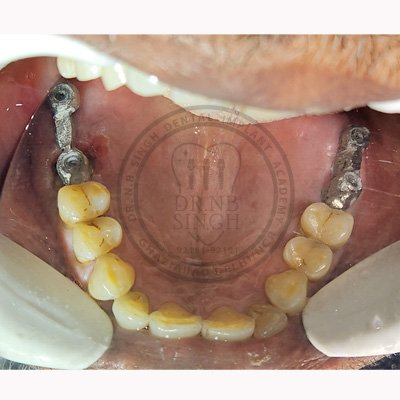

Case – 11 Baleram